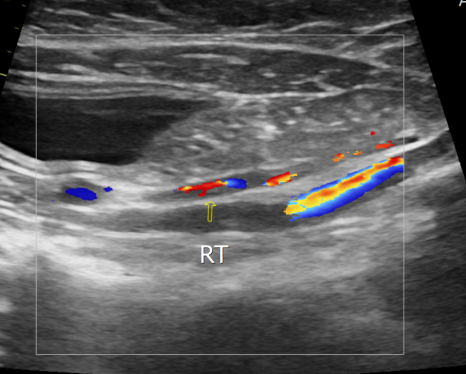

복부 대동맥 초음파 검사 / 출처: 24시온숲동물의료센터

복부 대동맥 초음파 검사

복부 대동맥 분지부와 대퇴동맥 내에서 국소적 혈전(폐색) 이 관찰되었습니다.

이러한 결과는 좌심방압 상승과 혈류의 와류로 인해 혈전이 형성된 전형적인 ATE의 기저 질환 패턴과 일치했습니다.